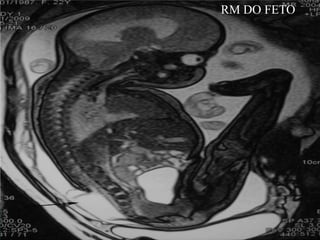

RM DO FETO